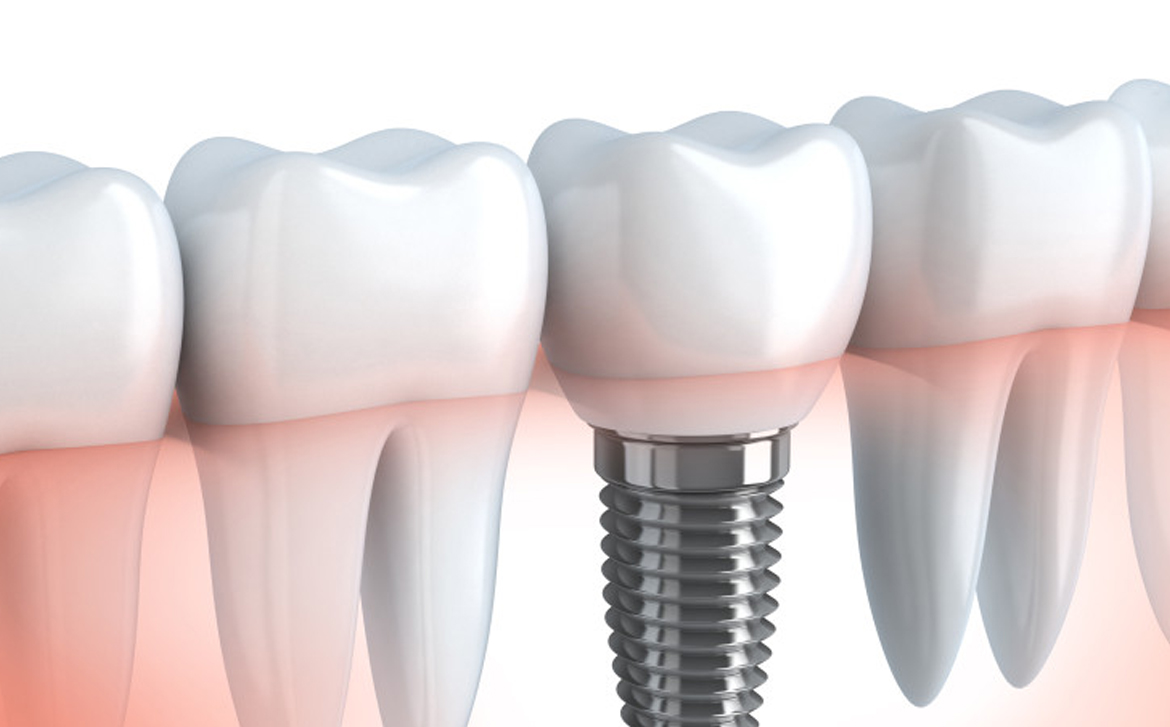

L’implantologia dentale è una tecnica avanzata che consente di sostituire uno o più denti mancanti in modo stabile e sicuro, senza coinvolgere i denti sani adiacenti.

Gli impianti sono radici artificiali in titanio biocompatibile, inserite nell’osso mascellare tramite un intervento chirurgico mini-invasivo, eseguito in anestesia locale.

È la soluzione ideale per sostituire un singolo dente mancante. L’impianto viene inserito nello spazio lasciato dal dente perso, senza limare i denti vicini. Garantisce un risultato funzionale, estetico e biologicamente conservativo.